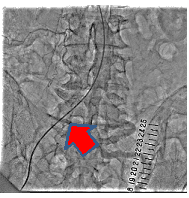

経皮的末梢動脈形成術の一例

- 【1】術前

- 【2】ワイヤー通過

- 【3】ステント留置

- 【4】術後